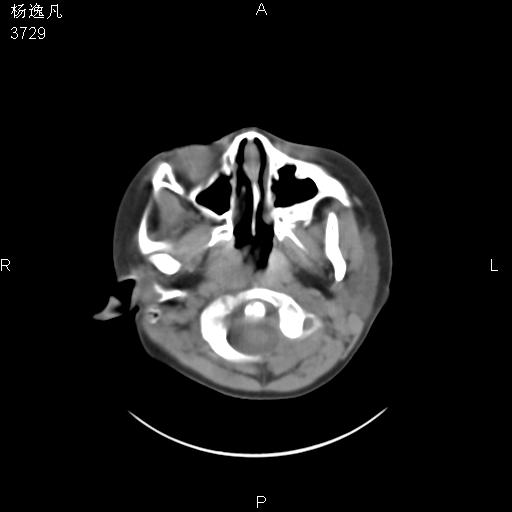

男性,5岁,面部受外伤,余无特殊

骨窗

鼻咽顶后变窄。顶后壁增厚,考虑腺样体肥大。其它未异常/

头颅ct平扫未见明确外伤性征象,右侧面部及颞部软组织肿胀,后鼻腔软组织影增大,增厚,鼻咽顶部变窄,考虑鼻咽腺样体增值肥厚。

双侧位置太不对称,未见明显骨折征象。